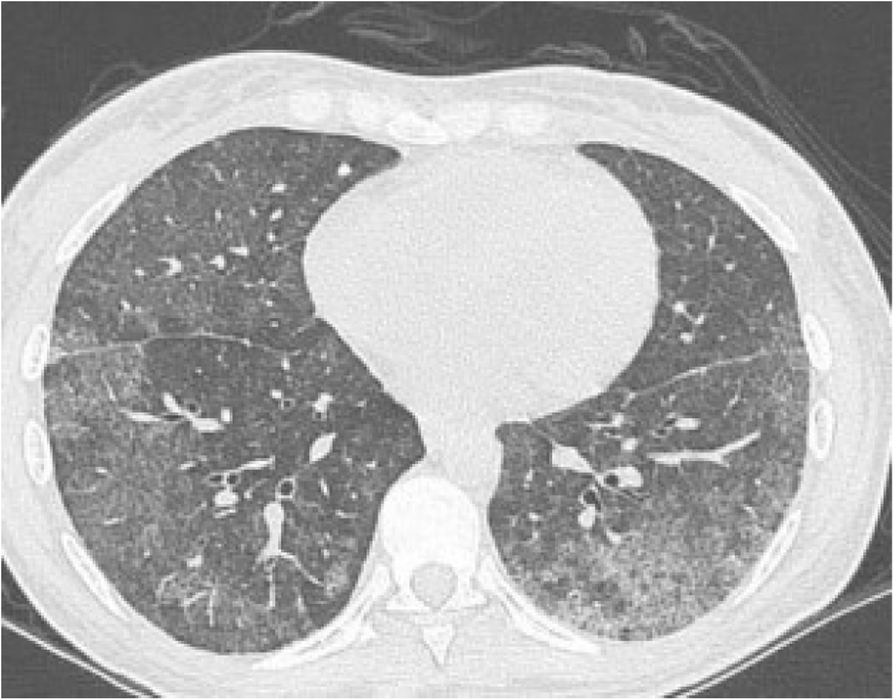

Fig. 1 (abstract P451).From: XXXV Brazilian Congress of Rheumatology (SBR 2018)Interstitial Infiltrate, suggestive of NSIPBack to article page